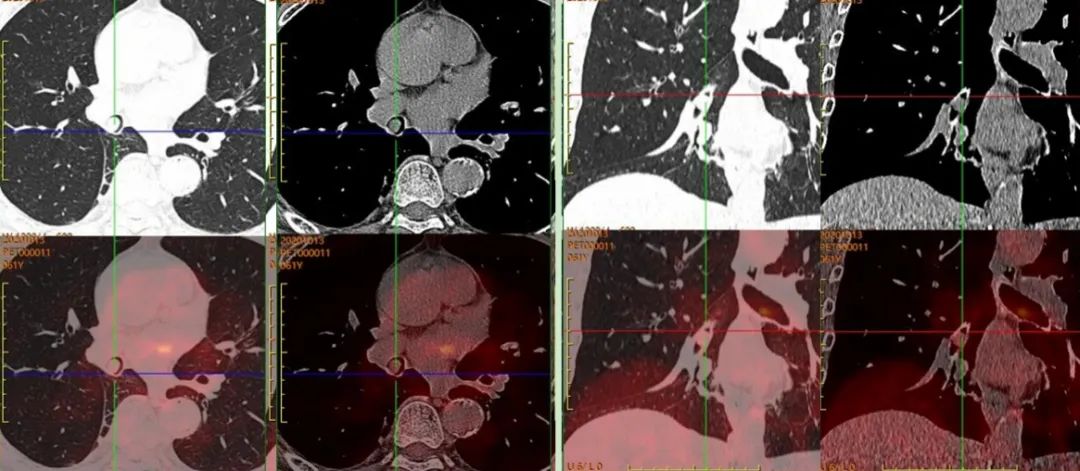

患者于上級醫(yī)院行氣管鏡檢查,病理考慮為“惡性腫瘤”。后來我院行PET/CT,完善治療前檢查。

圖2,PET/CT示右肺中間段支氣管結(jié)節(jié),早期SUVmax約1.8,延遲SUVmax約1.9,呈低代謝表現(xiàn);全身其余部位未見惡性腫瘤證據(jù);考慮為孤立的、單發(fā)的支氣管腔內(nèi)腫瘤,建議患者病理檢查。

患者后于上級醫(yī)院手術(shù)治療,術(shù)后病理為“支氣管錯構(gòu)瘤”。